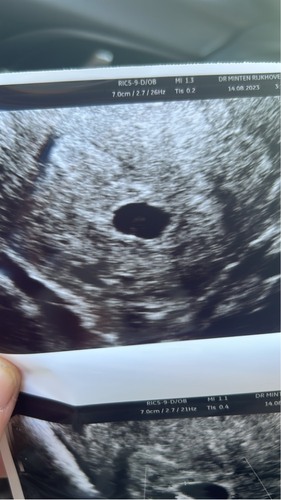

M鈥檔 eerste echo, straks terug bellen voor nieuwe echo eind augustus omdat ik nog maar 5 weken was we dachten langer 馃馃徎馃馃徎

Eerste echo op 16-8 met 6 weken. Vruchtzak met een vruchtje erin te zien. Volgende week 23-8 een tweede echo voor hartactiviteit